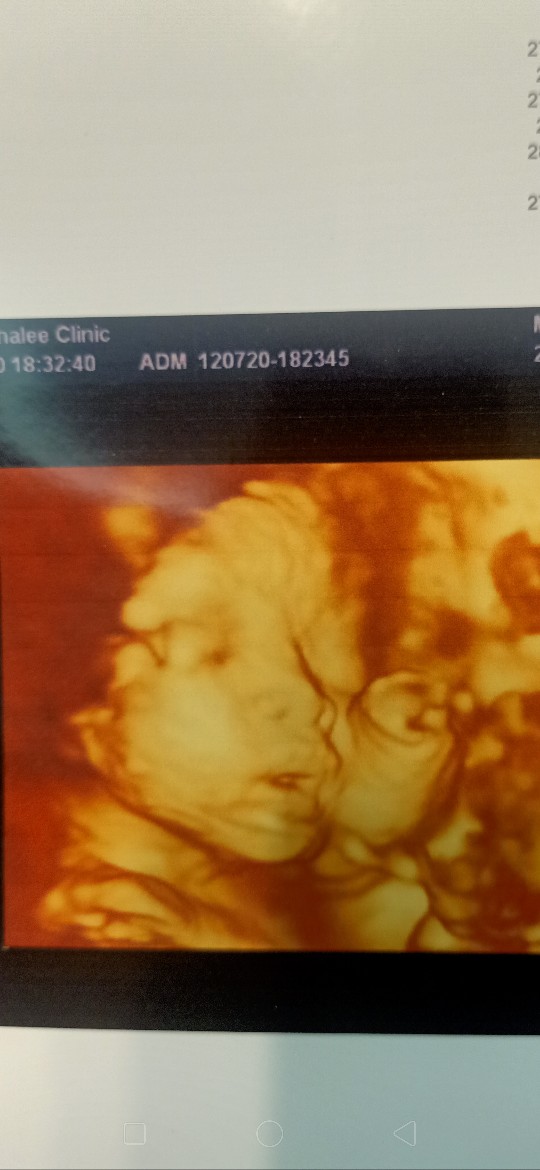

บ้านนี้ได้ลูกสาว ซาวด์ตอน27+1วีคจ้า กำหนดคลอดเดือนตุลาคม คุณหมอบอกน้องแก้มเยอะมาก แต่ไม่มีดั้ง🤣